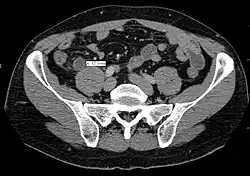

CT scan showing acute appendicitis

A CT scan demonstrating acute appendicitis (note the appendix has a diameter of 17.1 mm and there is surrounding fat stranding).

A fecalith marked by the arrow that has resulted in acute appendicitis.

Where it is readily available, computed tomography (CT) has become frequently used, especially in people whose diagnosis is not obvious on history and physical examination. Although some concerns about interpretation are identified, a 2019 Cochrane review found that the sensitivity and specificity of CT for the diagnosis of acute appendicitis in adults was high.[63] Concerns about radiation tend to limit use of CT in pregnant women and in children, especially with the increasingly widespread usage of MRI.[64][65]

The accurate diagnosis of appendicitis is multi-tiered, with the size of the appendix having the strongest positive predictive value, while indirect features can either increase or decrease sensitivity and specificity. A size of over 6 mm is both 95% sensitive and specific for appendicitis.[66]

However, because the appendix can be filled with fecal material, causing intraluminal distention, this criterion has shown limited utility in more recent meta-analyses.[67] This is as opposed to ultrasound, in which the wall of the appendix can be more easily distinguished from intraluminal feces. In such scenarios, ancillary features such as increased wall enhancement as compared to adjacent bowel and inflammation of the surrounding fat, or fat stranding, can be supportive of the diagnosis. However, their absence does not preclude it. In severe cases with perforation, an adjacent phlegmon or abscess can be seen. Dense fluid layering in the pelvis can also result, related to either pus or enteric spillage. When patients are thin or younger, the relative absence of fat can make the appendix and surrounding fat stranding difficult to see.[67]